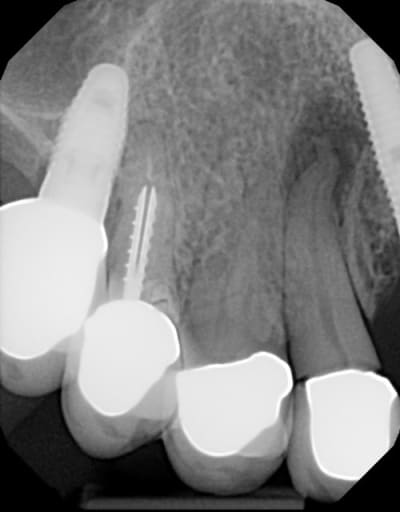

Patiente adressée pour évaluation :

son dentiste ne sait que faire.

À l'examen :

13 : belle fistule vestibulaire, mobilité, carie cervicale

14 : mobilité +++

15 : fracture racine (?), carie cervicale

Les implants datent de 5-6 ans (par un autre CD, la patiente a depuis déménagée).

Le bas , pas touche cette année, on verra en 2012.

Votre plan de tx ?

flicflac

08/04/2011 à 05h57

je le réfère à Céramik, il pose des implants...

Panorex avec Vitallium en bouche ok... au moins on sait que la patiente possède un partiel...

mobilité dent 14 sondage=?... perte sûre de la 15, endo et reprise couronne dent 13